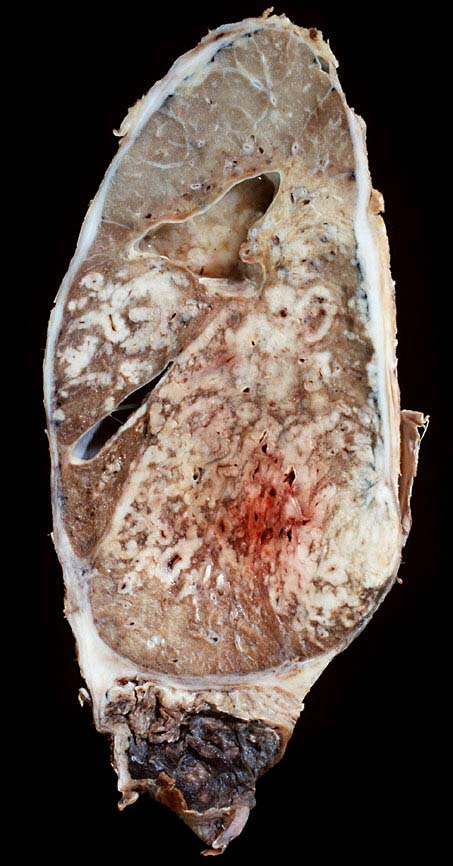

PathoPic ID 9089 - Kleinzelliges Bronchuskarzinom extensive disease

Kleinzelliges Bronchuskarzinom extensive disease

Ausgeprägte Lymphangiosis carcinomatosa und Tumorinfiltration der Pleura.

Nikotinabusus. COPD. Kleinzelliges Bronchuskarzinom, extensive disease. Chemotherapie und Radiotherapie.

Makroskopie